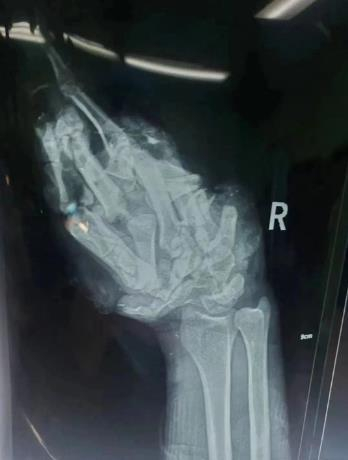

然而对医生们来说,考验才刚刚开始。刘本全介绍,以前接诊过的绞肉机绞手案例,患者多为一根、两根手指被绞,而此患者整个右手被绞,受损情况十分严重。经检查诊断,患者右手严重挤压毁损伤,手腕及手掌、手指多平面撕脱离断,手部掌指骨多发粉碎性骨折脱位,右手皮肤大面积撕脱伤伴缺损。在场大部分医护人员,包括手外科的年轻医护面对此情况都认为患者只能截肢了。

手术第一步是清创,手术团队对伤口进行仔细清创,清创伤口内坏死的组织和异物,同时仔细寻找细如发丝的每个血管神经断端,并仔细判断损伤的血管是否还可以使用并逐一标记,粉碎的骨块一块块拼合在一起并逐一固定,断裂的韧带、肌腱关节囊逐一认真地修复。“患者手部受损严重,其实从片子上已经分辨不出来手指了,骨头、血管都是多平面的断裂,血管也就比头发丝粗一点,整个清创探查过程就用了三个多小时。固定患者的骨折部位,这一步也用了两个多小时。”